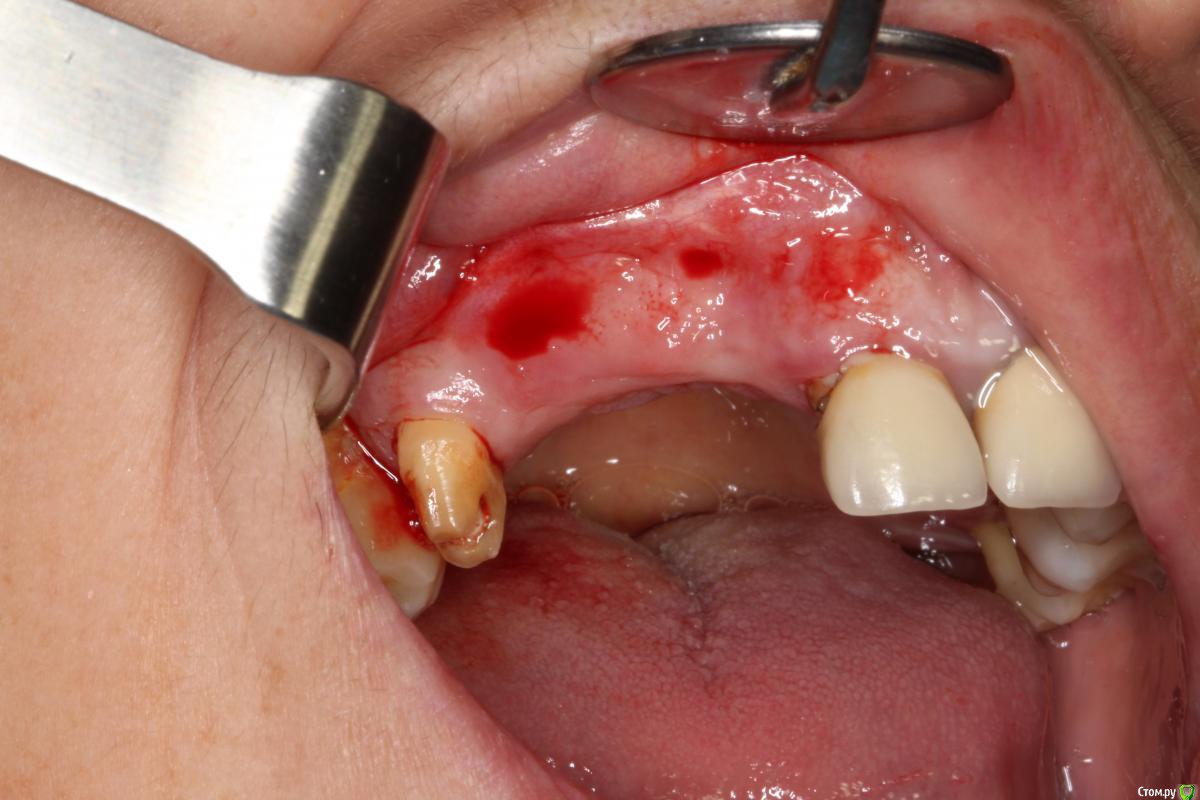

Robinbobin Опубликовано 9 сентября, 2015 Поделиться Опубликовано 9 сентября, 2015 Зуб 1.1 удалил,кюретаж и одномоментно установлен имплантат, заполнил MP3 и закрутил заглушкуУстановил имплантаты в области 1.3,1.4 подсыпал так же MP3 под мембрану и запинилЕсли покажите пальцем на ошибки буду благодарен))) 4 Ссылка на комментарий

колесников Опубликовано 9 сентября, 2015 Поделиться Опубликовано 9 сентября, 2015 Одномоментно желательно глубже ставить ,до 2мм по гребню уходит в последствии. У 12 обязательно сст . Впрочем можно было и в обл 13,14 им обойтись,но это дело вкуса. П-образный шов препочтителен,не будет расхождений и дополнительный объем на вершине получается. Ссылка на комментарий

zzkz Опубликовано 10 сентября, 2015 Поделиться Опубликовано 10 сентября, 2015 кмк можно ССТ положить и не аугментироваться в обл 13,14 Ссылка на комментарий